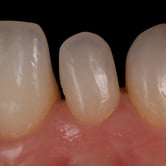

Dientes descoloridos

La decoloración dental es el cambio de color en los dientes debido a manchas superficiales o profundas causadas por alimentos, bebidas, tabaco, envejecimiento o medicamentos.

Los pacientes notan que sus dientes tienen un tono amarillento, marrón o incluso gris.

El tratamiento incluye blanqueamiento dental profesional, carillas o coronas para restaurar el color natural de los dientes.